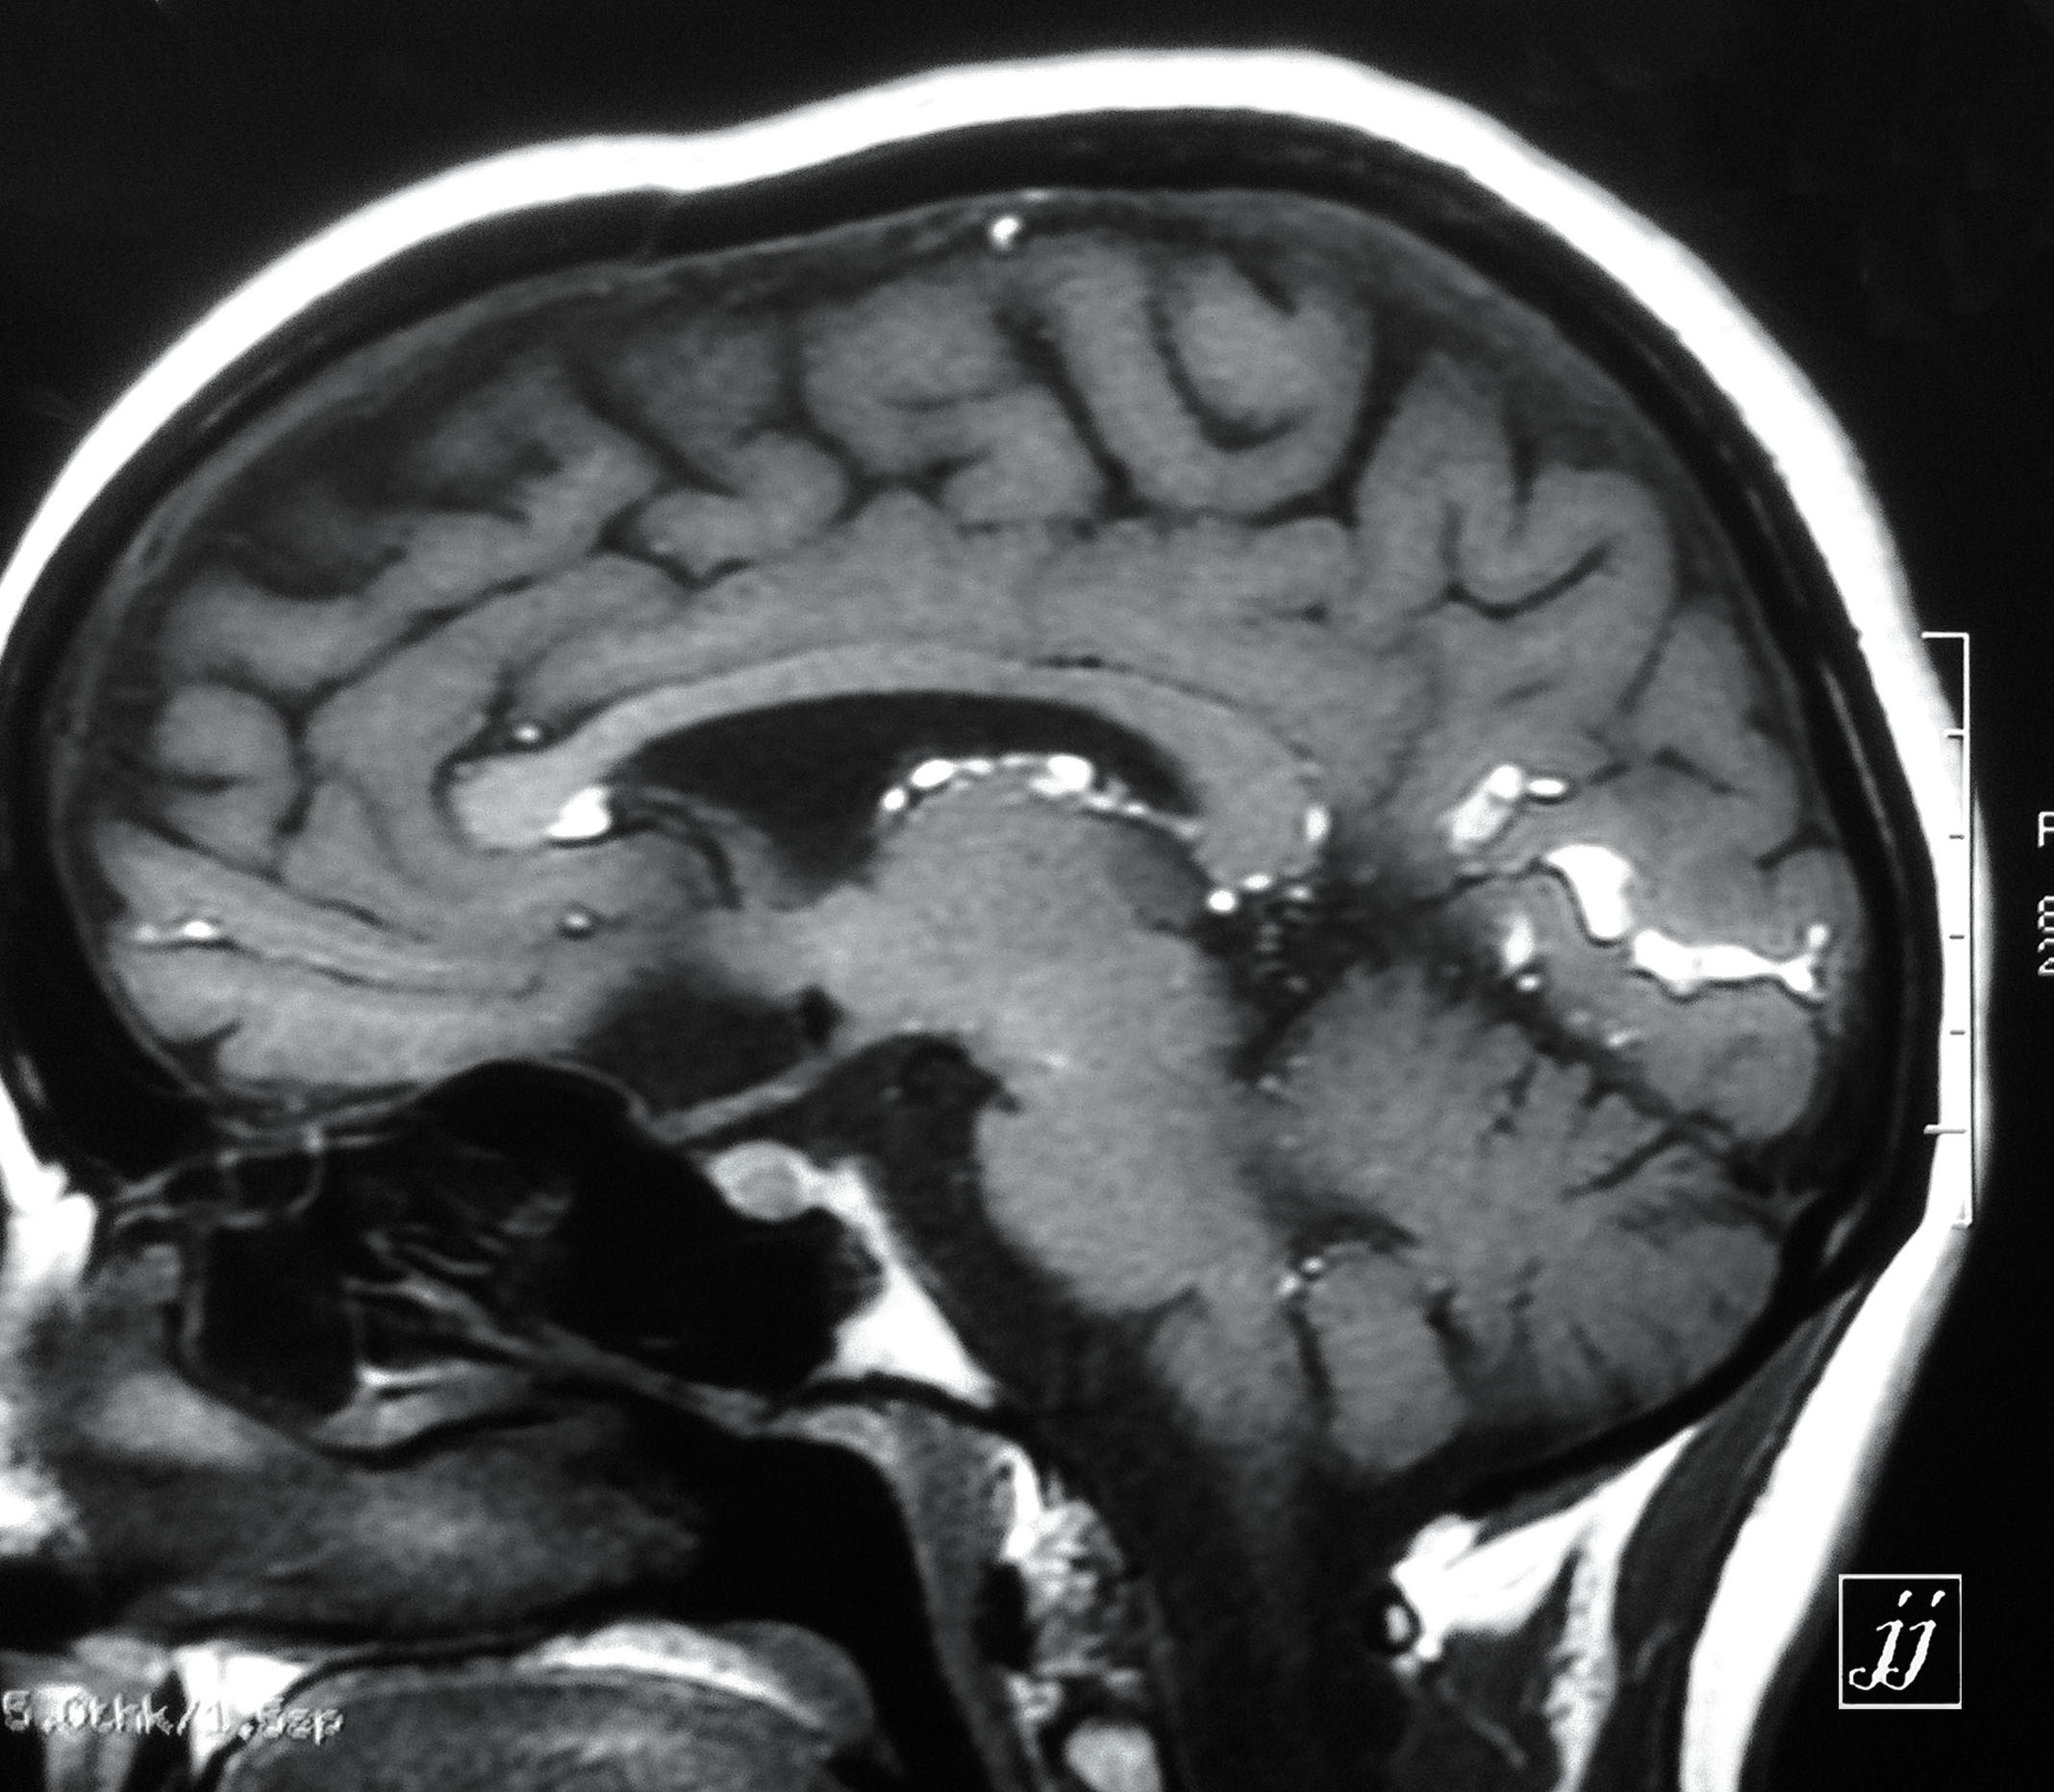

Brain- opac material in cisterns (8)